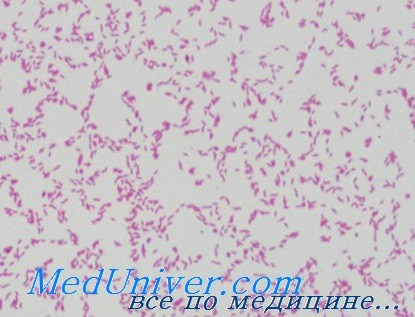

Кампилобактер фетус: патогенез и инфекции